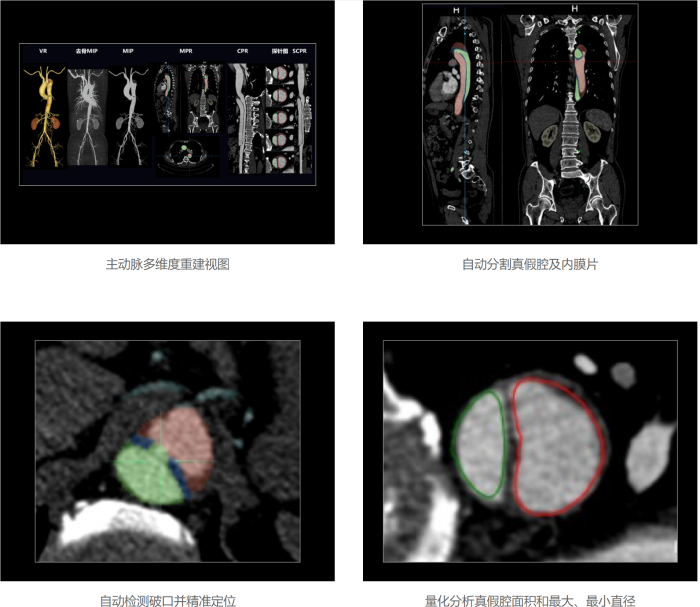

联影智能CTA主动脉智能分析系统支持主动脉及分支动脉秒级精准重建,自动生成VR、MIP、CPR、MPR等多维度视图,可大幅节省医生手动重建时间;系统同时支持自动检测和定位破口,自动定位关键解剖点,自动输出真假腔横截面积和最小直径等量化分析参数,辅助医生精准快速决策;此外系统还提供主动脉夹层分诊预警信息,可帮助医生尽早识别主动脉夹层患者,缩短患者诊疗时间。

联影智能CTA主动脉智能分析系统实现秒级精准重建,自动生成多维度视图,显著提高诊断效率。此外,系统通过自动检测和定位破口,提供量化分析参数,辅助医生快速准确做出诊断,减少漏诊和误诊。在夹层预警方面,系统能及时提供分诊预警信息,并支持双端智能分诊,帮助医生尽早识别主动脉夹层患者,缩短诊疗时间。